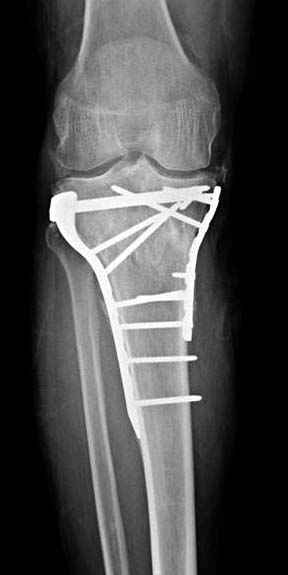

Решили выполнить остеосинтез штифтом и внутрисуставного перелома пластиной и винтами. Жду мнения! Зачем мне оправдываться-я же не преступник. Диалогом называется...

Отдельные переломы тибиал плато и перелом проксимальной трети большеберцовой кости отличаются от переломов тибиал плато с вовлечением диафиза. Здесь перелом тибиал плато типа Schatzker VI, полученный в результате высокоэнергетической травмы. Перелом метафиза образовал отрыв суставной поверхности от диафиза с вовлечением медиального и латерального мыщелков. Двухмыщелковые переломы из-за укрочения опасны развитием компартаментального синдрома, повреждением латерального мениска и связок.

При переломах одного из мыщелков тибиал плато+дополнительный перелом проксимальной трети большеберцовой кости можно применить комбинированный вариант фиксации, т.е. мыщелок винтами или пластиной, а для диафиза можно установить гвоздь. В данном варианте потеряно преимущество гвоздя , из-за серьезной травмы суставной поверхности нельзя нагружать ногу несколько месяцев. А без нагрузки гвоздь просто заполнитель пространства внутри кости!

На вашем место я бы подождал с фиксацией до готовности кожных покровов, и за это время можно было подобрать соответствующий фиксатор, т.е более длинная пластина снаружи и медиальная пластина на апексе перелома как подпорка. Здесь приемлем как раз минимальный доступ.

Имеющаяся импрессия не потребовала пластики - достаточным оказалось поднять отломок

Если там действительная импрессия, пустое место без структуральных заполнителей, кость или синтетические материалы, не восстановится, а образуется коллапс, и ось конечности поведет после нагрузки. Кроме того там возможно "болт стяжка"?, в медиальной стороне выступает за кортекс, можно было укоротить! Потом создается впечатление, что не соответствуют мыщелки большеберцовой и бедренной костей? Покажите снимок.

Здесь пару случаев для сравнения,...в первых 1-4 слайдах метод фиксации одним фиксатором, как видно после 8 месяцев сохранилась ось. С 5 по 9 вариант двумя пластинами...